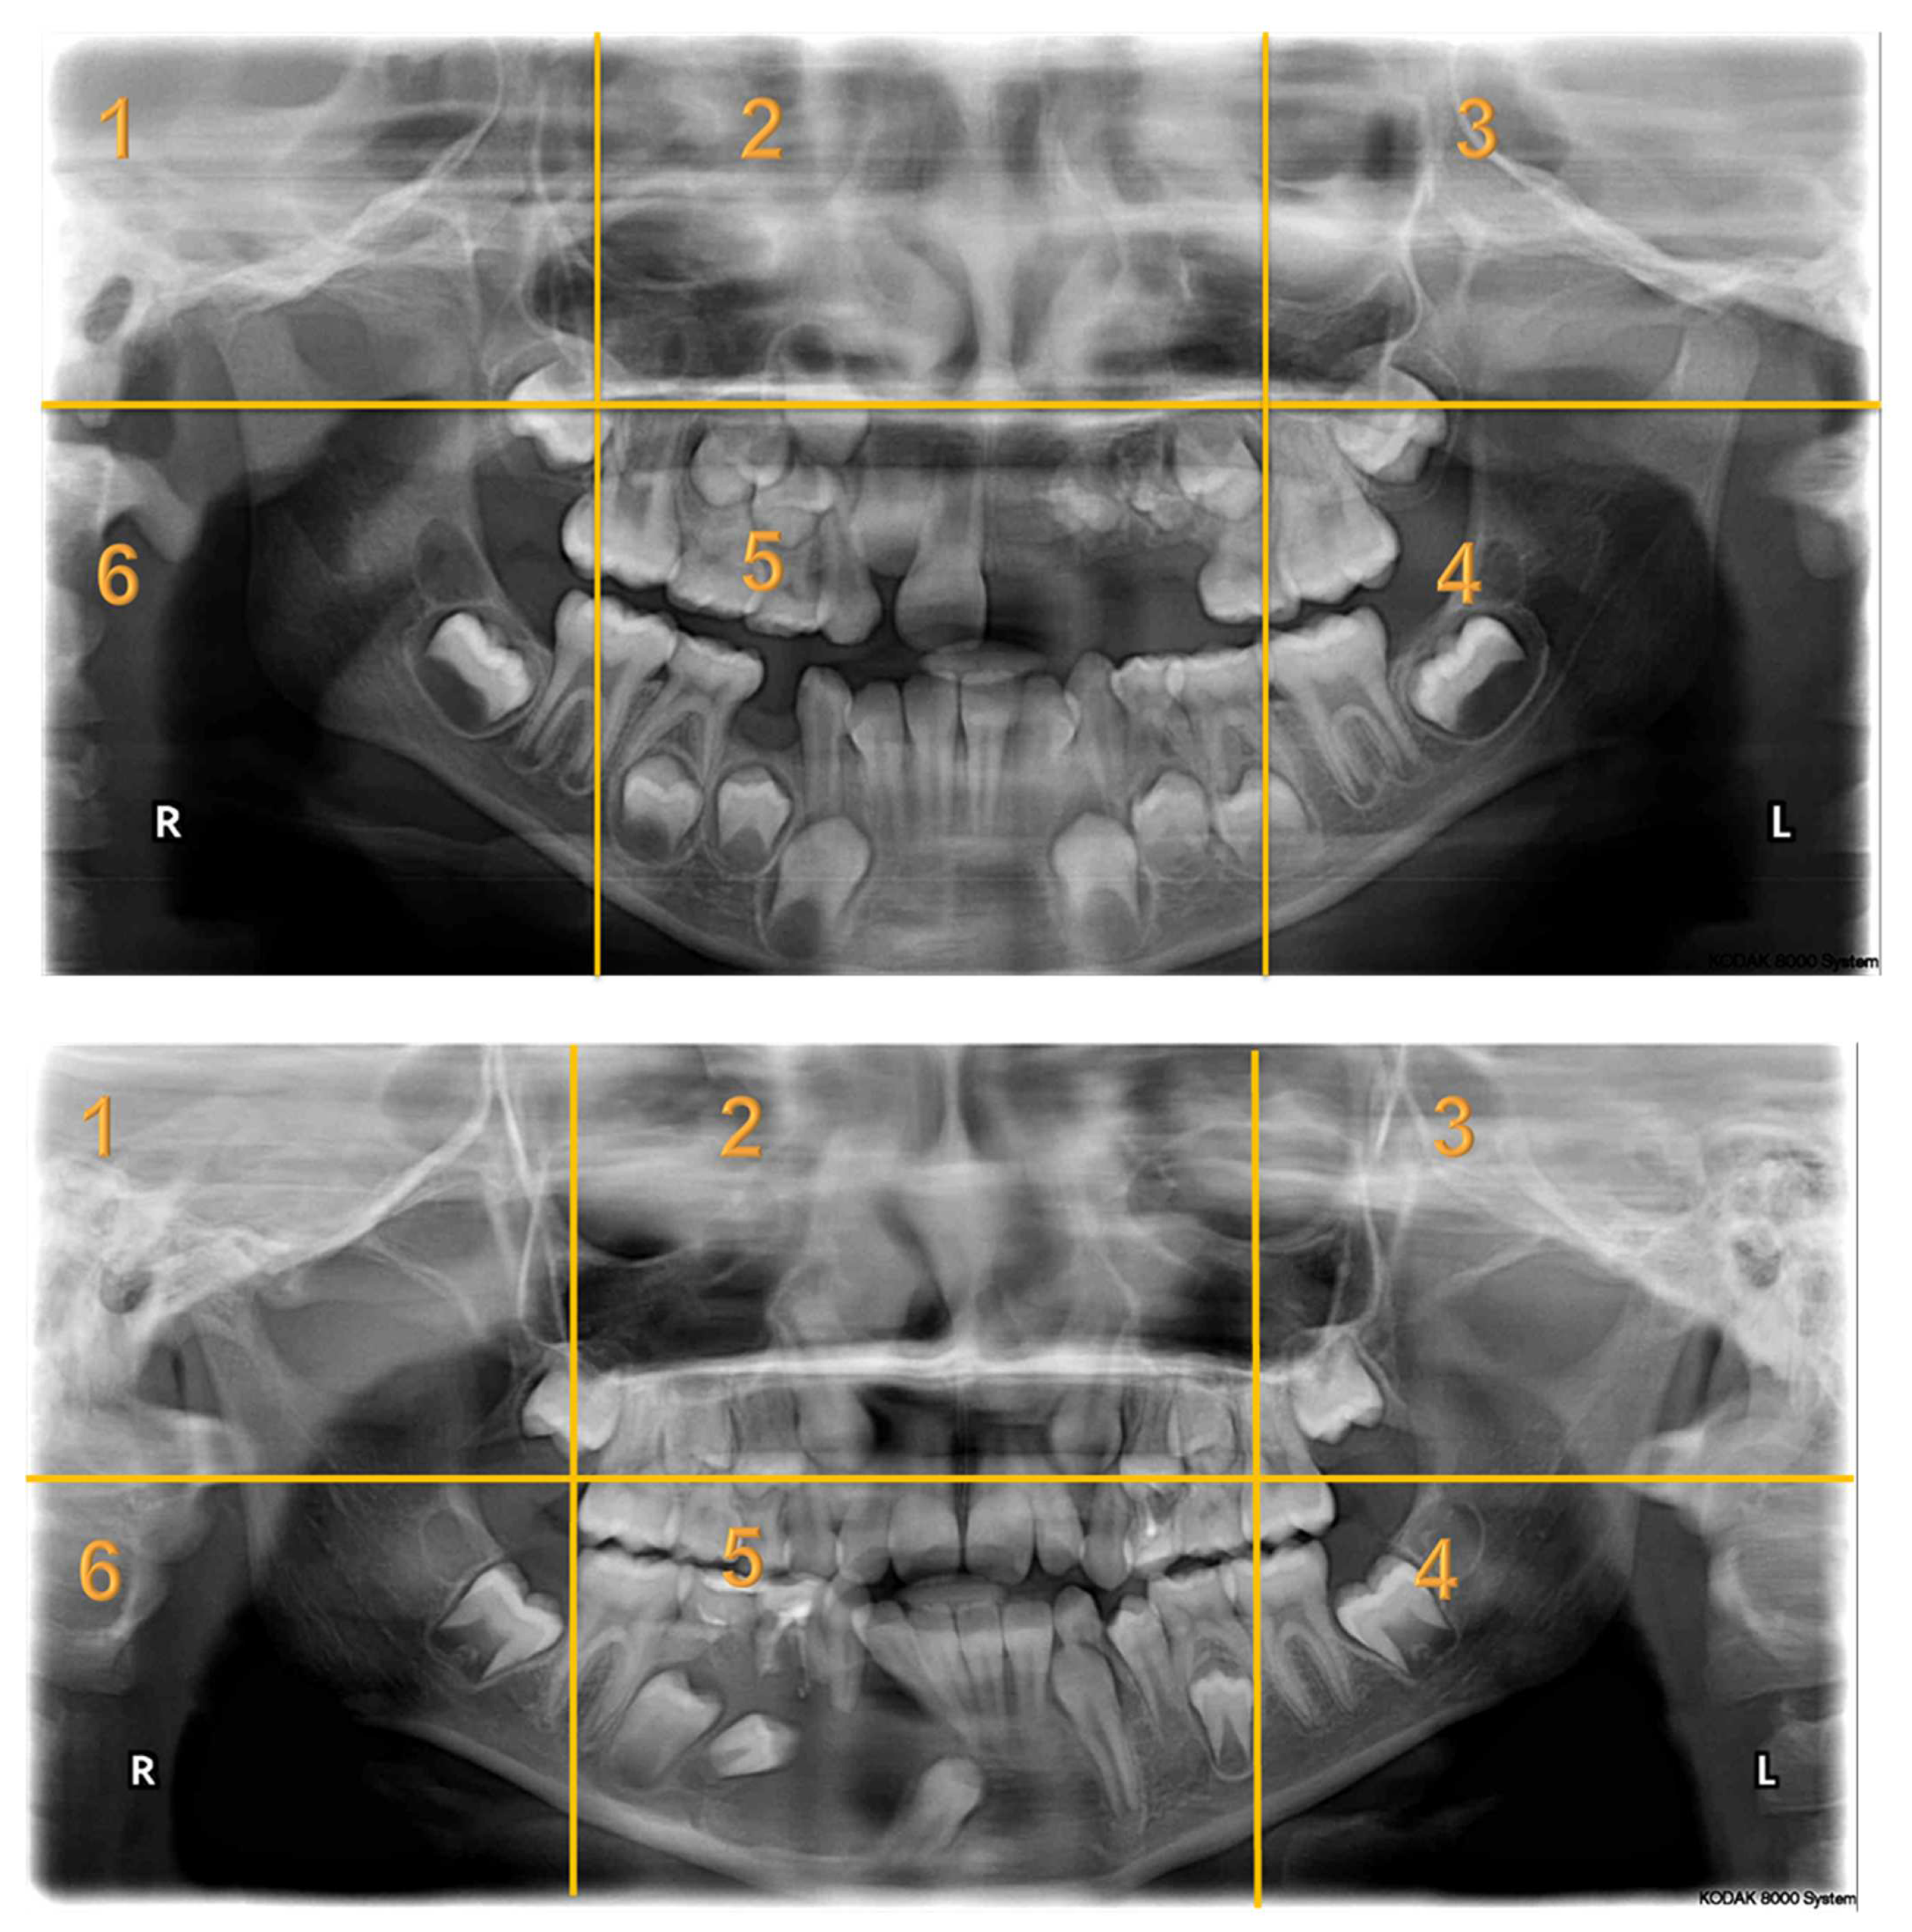

Appendix A. Radiographs Included in the Study

- Each panoramic radiograph displayed will be divided into sextants by yellow lines.

| Radiographs with Abnormalities | Number of Sextants Involved | Number of AOI a | Number of Participants | Total Recorded Observation b |

|---|---|---|---|---|

| Radiograph 1 | Multiple | 3 | 30 | 90 |

| Radiograph 2 | Multiple | 8 | 30 | 240 |

| Radiograph 3 | Single | 2 | 30 | 60 |

| Radiograph 4 | Single | 2 | 30 | 60 |

| Radiograph 5 | Single | 1 | 30 | 30 |

| Radiograph 6 | Single | 1 | 30 | 30 |

| Radiograph 7 | Single | 1 | 30 | 30 |

| Overall Observations | 540 |